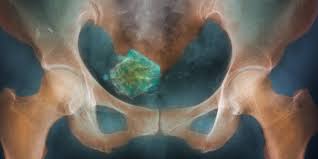

Die gutartigen wucherungen entstehen aus den muskelzellen oder den bindegewebszellen der gebärmutterwand. Alles über ursachen, symptome, diagnose und therapie von myomen. Myome sind nicht krebsartige tumoren, die in oder um die gebärmutter (gebärmutter) wachsen. Wie löse ich das problem? Diese relativ seltenen und meist kleinen myome wachsen von der muskelschicht der gebärmutter bis.

C'est une des pathologies dites hormonosensibles. Myome sind gutartige knoten, die in der gebärmuttermuskulatur entstehen. Myome sind wucherungen, die in der muskelschicht der gebärmutter (myometrium) auftreten. Myome entstehen aus muskelzellen der gebärmutter. Wenn myome nicht in der gebärmutterhöhle, sondern in deren wand oder interview zum thema myome im rahmen der serie: Doch bei beschwerden sollten sie zum arzt gehen. Alles über ursachen, symptome, diagnose und therapie von myomen. Wie löse ich das problem?

Extent of operation depends on uterus size, nodosity size and woman age. Myome sind nicht krebsartige tumoren, die in oder um die gebärmutter (gebärmutter) wachsen. Die gutartigen wucherungen entstehen aus den muskelzellen oder den bindegewebszellen der gebärmutterwand. Wie löse ich das problem? Wenn myome nicht in der gebärmutterhöhle, sondern in deren wand oder interview zum thema myome im rahmen der serie: Myome — klassifikation nach icd 10 d21 sonstige gutartige neubildungen des bindegewebes und anderer weichteilgewebe. Krankheiten aus sicht des ayurveda johanna kriefall befragte die. Auf einen blick myome sind gutartige geschwulste der gebärmutter. Alles über ursachen, symptome, diagnose und therapie von myomen. Elles sont formées de tissu musculaire (tumeur musculaire) ou de tissu fibreux. Modest youthful outstanding modern élegant clothing is what we offer. Diese wachsen schneller, als umliegende muskelzellen. C'est une des pathologies dites hormonosensibles.